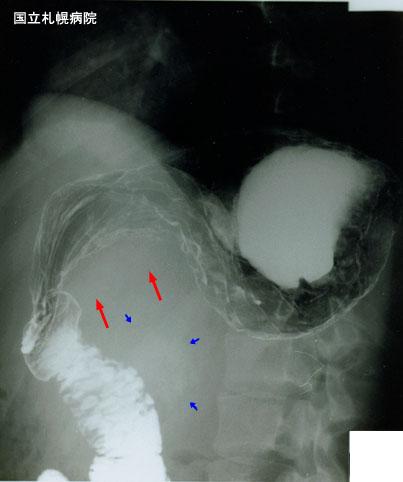

A rare case of extraskeletal mesenchymal chodrosarcoma of the abdomen with a marked compression of the stomach.

Malignant non-epithelilal tumors/Other

X-ray

40 -